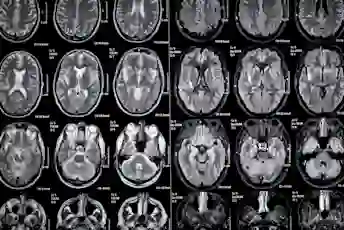

从您的MRI中有意义

这是这些年度灰度脑扫描对您的疾病进展的说法。